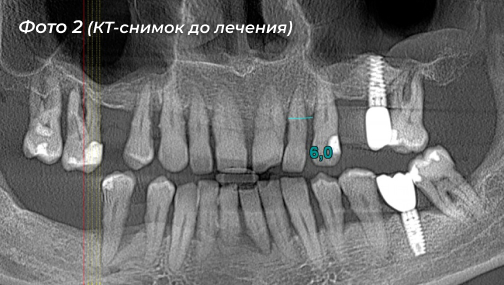

Проблема: пациент обратился с жалобами на подвижность всех зубов на верхней и нижней челюстях, жевать ими было очень сложно (Фото 1, 2).

Решение: сохранить зубы, к сожалению, было уже невозможно, так как оба зубных ряда качались. Совместно хирург Павлова Ольга Юрьевна  и ортопед Калинин Антон Сергеевич разработали поэтапный план лечения, направленный на восстановление полноценной жевательной функции и эстетики улыбки.